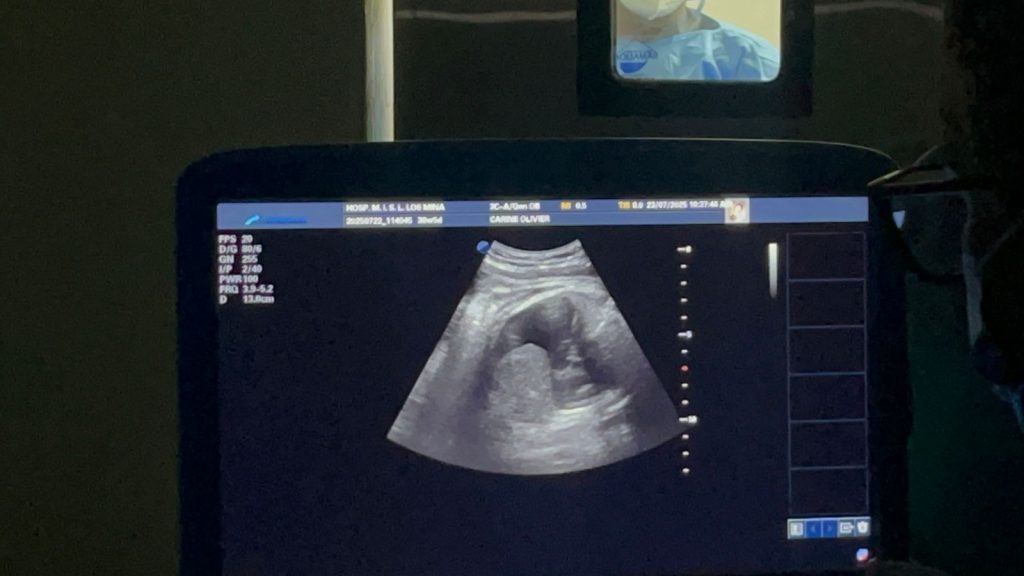

La intervención se desarrolló en dos etapas. En la primera, prenatal, los doctores Ramiro Díaz y Virginia Pérez realizaron un drenaje toracoamniótico para extraer líquido del espacio pleural y pericárdico que, de permanecer, habría impedido que la bebé respirara adecuadamente al nacer.